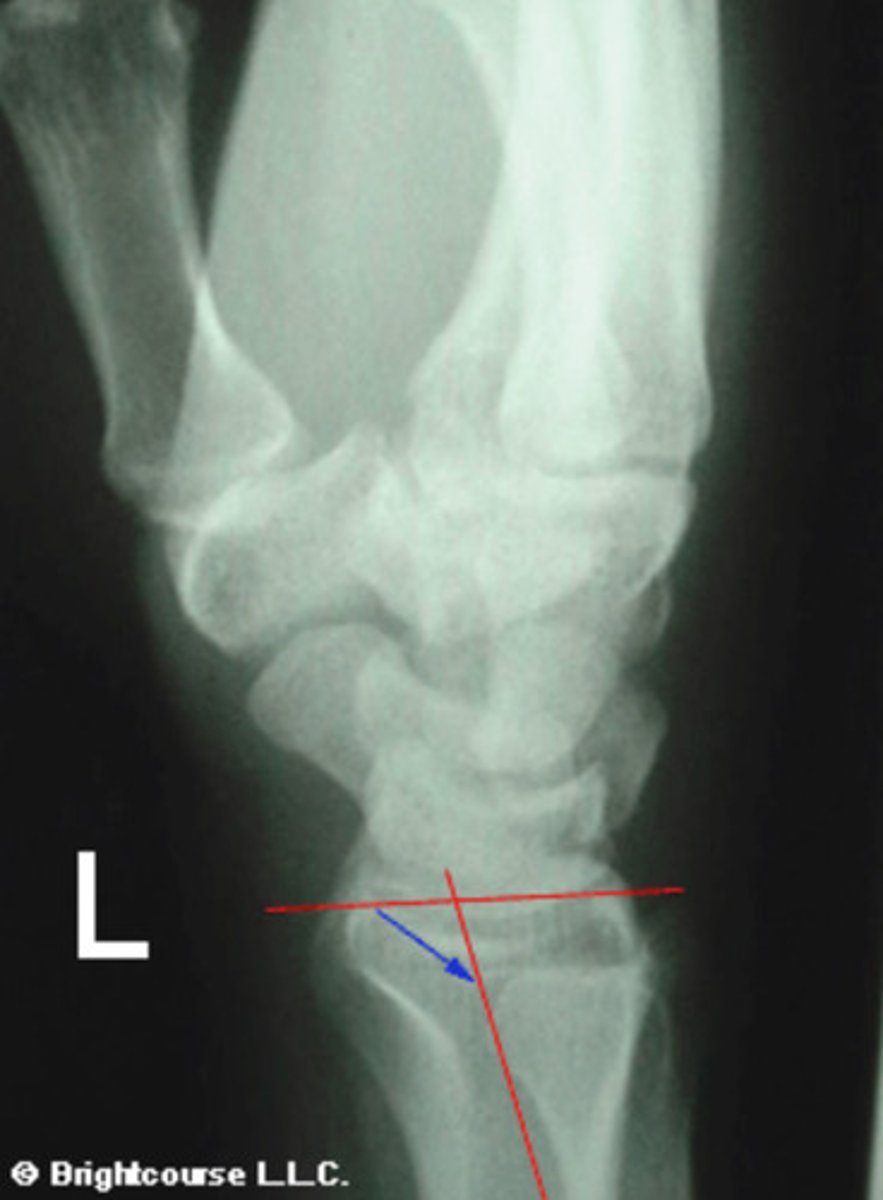

Radioulnar angle

What angle is being assessed in this image?